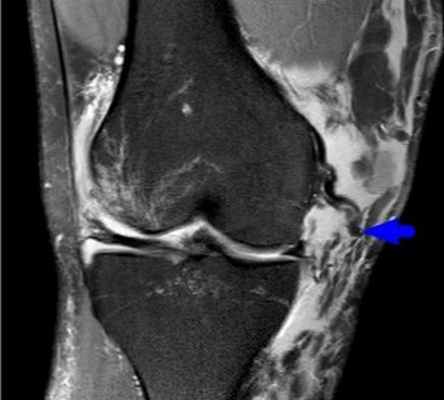

Подколенный бурсит

Подколенный бурсит (киста Бейкера). Особенностью подколенной серозной сумки является то, что в половине случаев она соединяется с полостью коленного сустава, поэтому в большинстве случаев гонартрит и подколенный бурсит развиваются одновременно. Причинами первичного подколенного бурсита являются травмы, микротравмы, перегрузка коленного сустава (в частности при нарушении статики), вторичного— ревматоидный артрит, гонартроз с реактивным синовитом и другие заболевания коленного сустава.

Киста Бейкера проявляется умеренными болями в подколенной ямке, усиливающимися при разгибании голени, иногда слабостью и онемением конечности (сдавление проходящего здесь большеберцового нерва). Подколенная ямка заполнена округлой эластичной опухолью, исчезающей при сгибании голени. Разгибание коленного сустава болезненно и ограничено. Иногда опухоль распространяется на верхнюю часть икроножной мышцы. При пункции кисты получают прозрачную жидкость, напоминающую синовиальную. Часто одновременно наблюдаются признаки артрита коленного сустава.